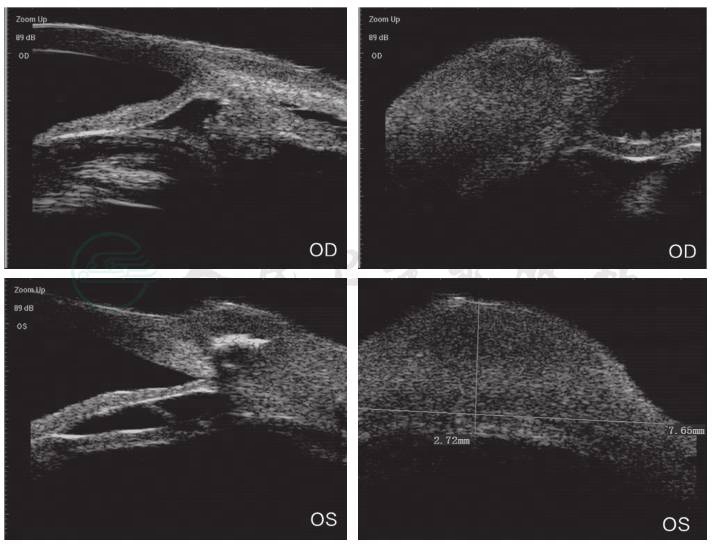

眼B超见左眼玻璃体混浊(图2)。UBM检查见中低回声巩膜隆起(图3)。对右眼巩膜肿物进行穿刺,取其内容物培养未见细菌、真菌等微生物生长。PET-CT见肋部软骨串珠样改变(图4)。

图2 患者门诊就诊时(2020年4月16日)眼B超见左眼玻璃体混浊

引自:主编:.同仁眼科疑难病例精析:同仁眼科临床病例讨论会1.第1版.ISBN:978-7-117-33030-5

鉴于患者角膜融解病程长、角膜及巩膜菲薄以及既往外伤和巩膜裂伤病史,在手术方式的选择方面,角膜专科与眼外伤专科进行了联合讨论:患者首次眼部B超发现左眼玻璃体混浊,首先考虑进行玻璃体切除联合人工晶状体置换术。后复查B超发现,玻璃体混浊仅局限于前部,后部安静且无视网膜脱离。于是考虑进行前部玻璃体切除。然而患者巩膜菲薄,难以进行常规玻璃体切除通道的建立。同时考虑角膜以及巩膜条件很差,不能进行角膜移植。为了安全地达到提高视力的目的,两科联合进行瞳孔成形联合IOL机化膜撕除的方式来为眼球创造一个光学通路。